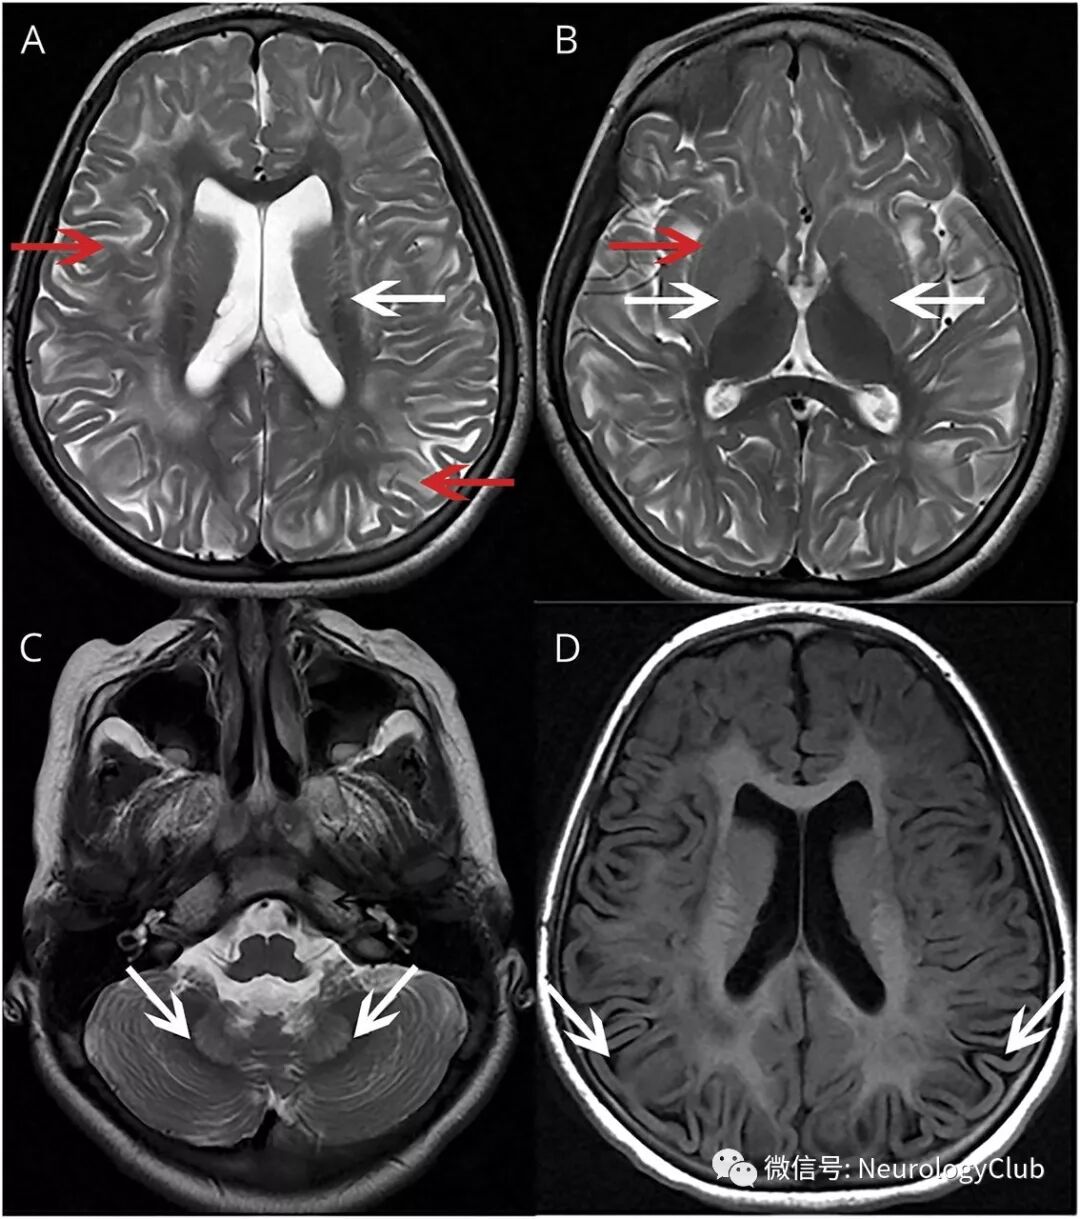

9岁女孩,5岁开始隐匿性出现行走困难,反复跌倒,焦虑和学习成绩不佳。患者MRI表现(图)提示典型的L-2-羟基戊二酸尿症(L2-HGA)。

(图:A:T2WI可见双侧对称性白质(WM)高信号[红箭],呈向心型分布,累及皮质下和深部WM,脑室周围WM不受累[白箭];B:基底节高信号[白箭]伴壳核边缘更高信号[外缘征outer rim sign,红箭];C:齿状核高信号[白箭];D:FLAIR可见脑组织稀疏[白箭])

其特征性MRI表现为散在或弥漫性大脑皮质下白质、基底节(苍白球、尾状核和壳核——按出现频率由多到少)和小脑齿状核长T2信号和脑萎缩,皮质下白质异常呈向心性减轻与其他白质脑病不同。